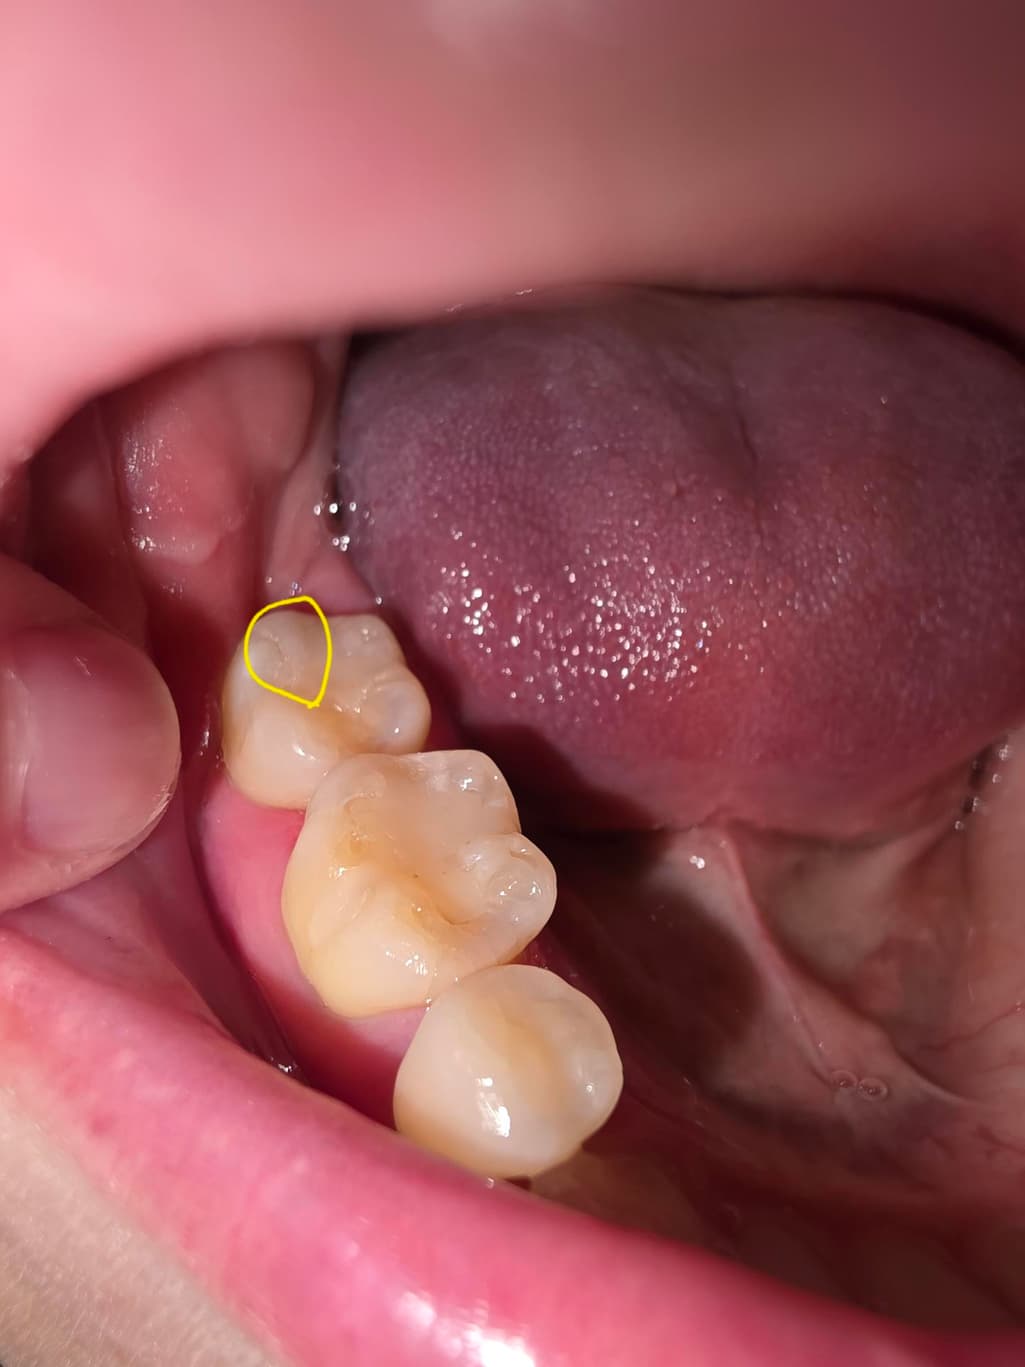

레진한 부분에 생긴 스크레치난 부분 치과가서 연마 해야될까요? ㅠㅠ

이러면 안돼는거 알지만... 충치인지 바늘가지고 치아 긁어보다가 레진쪽을 긁었는데요.. 중간 사진 처럼 긁혀있다가 양치하고 나니 마지막 사진 처럼 스크레치가 남아있는데 양치로는 스크레치 없어지지 않을까요? 지피티나 제미나이에게 물어보니 2차우식이나 착색 때문에 연마하는게 좋다고 그래서요... ㅠㅠ 치과가서 연마가 필요한지 궁금합니다.

• 3번 째 사진